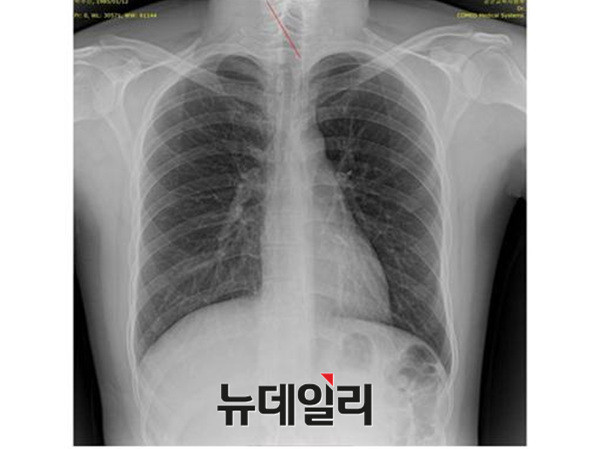

- ▲ 박주신씨 명의의 자생병원 엑스레이. ⓒ 뉴데일리DB

반면 지난해 12월부터 시작된 양승오 박사 등 시민 7명에 대한 공직선거법 위한 공판을 통해 새롭게 밝혀진, 박주신씨의 ‘공군훈련소 입소 당시 엑스레이’(촬영일자 2011년 8월 30일, 이하 공군 엑스레이)와, 주신씨가 ‘비자발급을 위해 촬영한 세브란스병원 엑스레이’(촬영일자 2014년 7월 31일, 이하 비자발급용 엑스레이)는 각각 박주신씨 본인의 신체를 촬영한 것으로 받아들여지고 있다.

이들 3개의 엑스레이는 모두 박주신씨의 신체를 촬영한 것으로 알려져 있기 때문에, 판독결과 피사체를 동일인으로 볼 수 없는 유의미한 차이점이 발견된다면, 이는 박주신씨의 대리신검 혹은 영상자료 바꿔치기 의혹을 뒷받침하는 유력한 단서가 된다.

영상의학전문의 양승오 박사(동남권원자력의학원 암센터 핵의학과 주임과장)와 치과의사 김우현 원장 등 박주신씨 병역비리 의혹을 주장해 온 시민들은, 위에서 언급한 3개의 엑스레이에 대한 비교 판독 결과, 이들 엑스레이를 같은 사람의 것으로 볼 수 없는 차이점을 발견하고 이를 재판부에 증거자료로 제출했다.

현재 피고인들은 주신씨 명의의 엑스레이 비교 판독 결과 나타나는 ①석회화 현상-②극상돌기 배열 방향-③흉곽의 모양-④기관(氣管)의 뻗은 모습 등을 근거로, 대리신검 혹은 영상자료 바꿔치기 가능성을 제기하고 있다.

박주신씨의 자생병원 X-Ray를 보면, 오른쪽 제1 늑골부위에 ‘석회화’ 현상이 나타난다. 그러나 주신씨가 공군 입대 당시 찍은 X-Ray에는 이런 모습이 전혀 보이지 않는다.

이런 차이에 대해 양승오 박사의 변호인인 차기환 변호사 등은 "각각의 X-Ray를 찍은 사람이 동일인이 아니라는 것을 입증한다"고 설명했다.